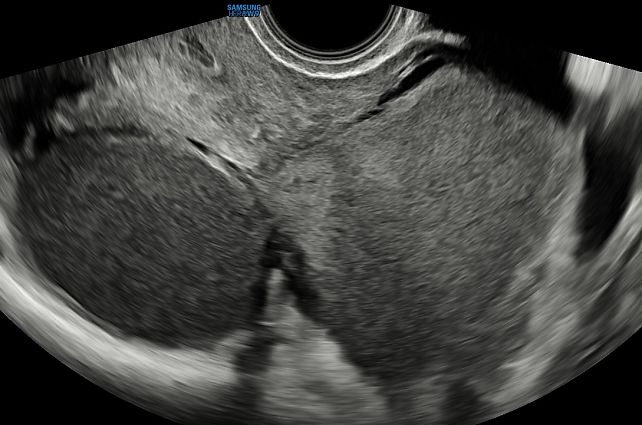

On ultrasound examination, typical endometriomas present as a cystic lesion with ground-glass echogenicity, with one to four locules and no solid components in a premenopausal patient (Figure 26). Of 713 histologically confirmed endometriomas in the International Ovarian Tumor Analysis (IOTA) studies, 65% were unilocular and 73% exhibited ground-glass echogenicity and 13% had low-level echogenicity.42 Atypical endometriomas are defined as unilocular-solid lesions with ground-glass echogenicity and a papillary projection, a color score of 1 or 2 and no vascularization inside the papillary projection (Figure 27).5 As per the recommendation of the IDEA consensus, the presence or absence of endometriomas should be described, as well as their number, size in three orthogonal planes and their ultrasound appearance according to International Ovarian Tumor Analysis (IOTA) terminology.43 Assessing vascularization by power Doppler may help in the differentiation between an endometrioma, a corpus luteum and a malignant lesion.44 A corpus luteum is characterized by strong circumferential blood flow (‘ring of fire’) and will generally resolve spontaneously after the menstrual cycle, unlike an endometrioma.

26

Ultrasound images of endometriomas with typical features of ground-glass echogenicity, up to four locules and no solid components.